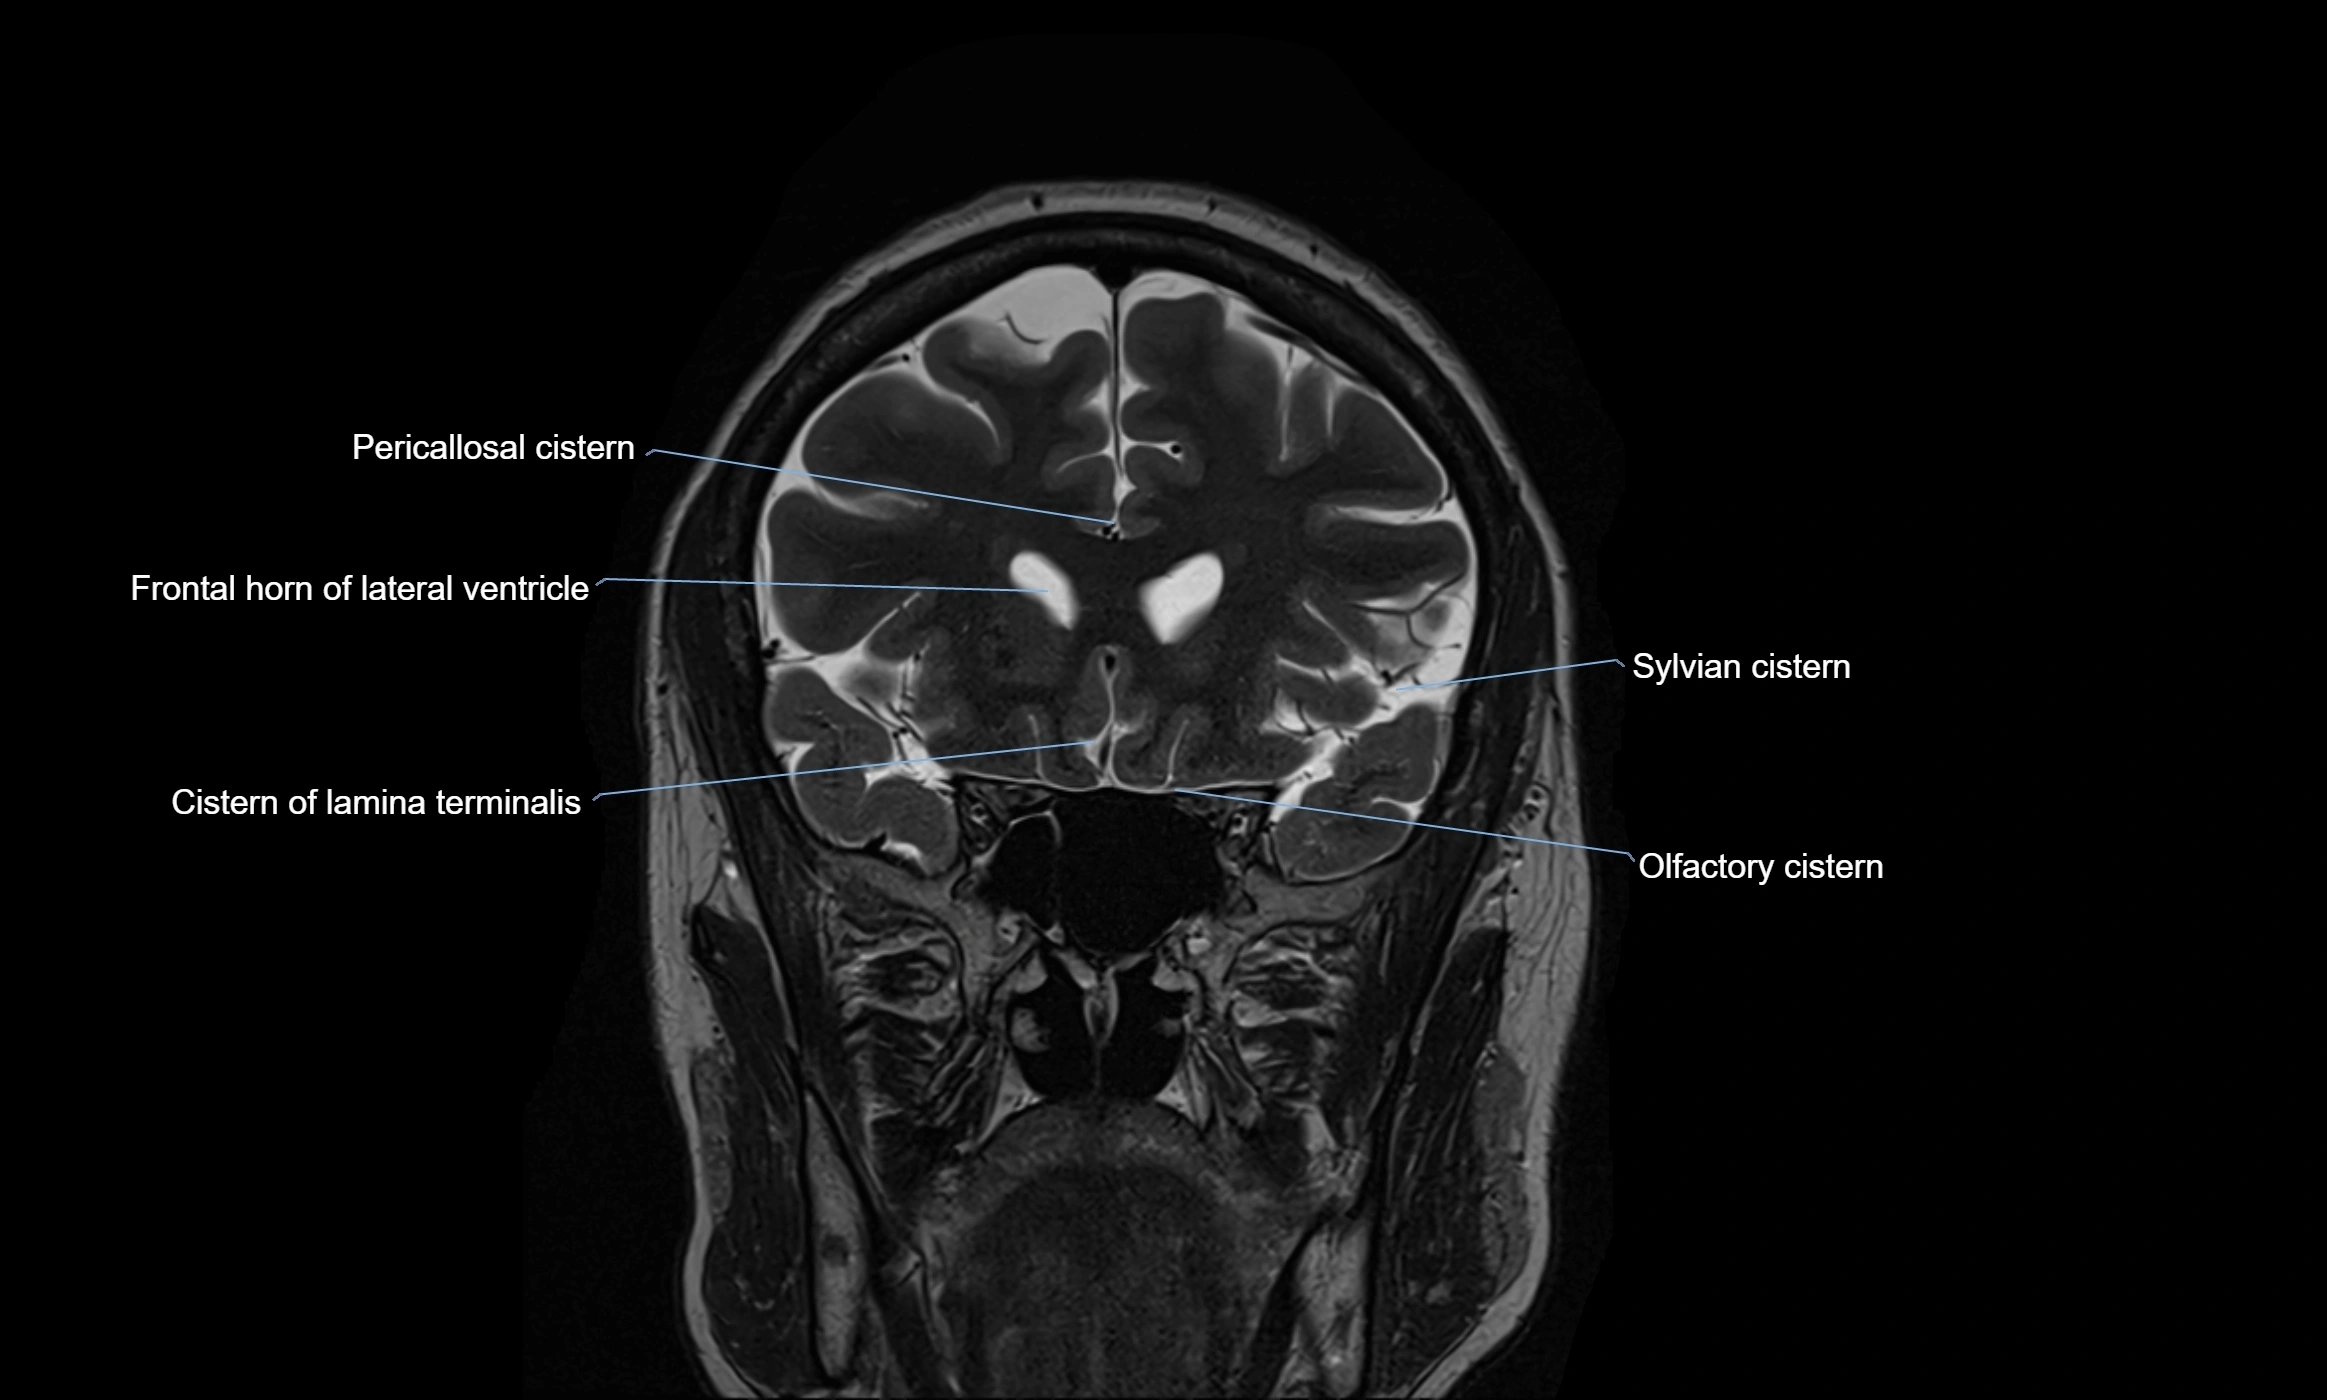

The ambient cistern is a paired, narrow, and elongated subarachnoid space located bilaterally along the lateral aspect of the midbrain. It serves as a conduit between the interpeduncular cistern anteriorly and the quadrigeminal cistern posteriorly. This cistern houses critical neurovascular structures, including parts of the posterior cerebral artery, superior cerebellar artery, trochlear nerve (cranial nerve IV), and the basal vein of Rosenthal. It plays an important role in the circulation of cerebrospinal fluid (CSF) and provides an anatomical corridor for various vessels and nerves passing around the midbrain.

MRI Appearance

• T2-weighted images:

• The cistern is hyperintense (bright) due to the high water content of CSF.

• Encapsulated vessels and nerves are seen as flow voids or hypointense lines within the bright background.